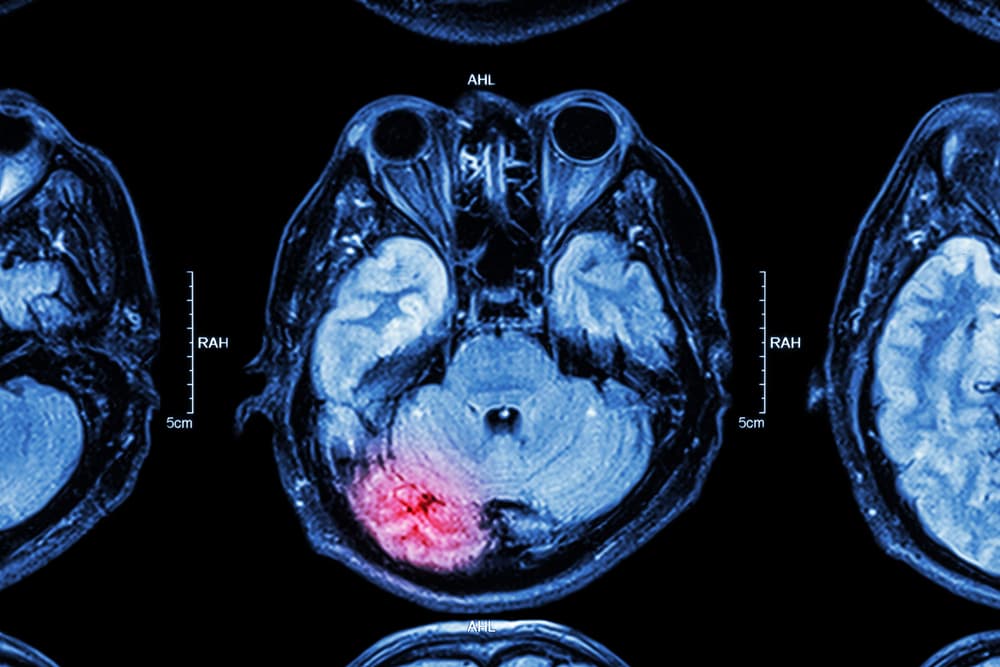

Moderate to severe TBIs require more intensive medical intervention. Emergency care is often the first step since stabilizing the accident victim is critical. Doctors work to ensure proper oxygen supply to the victim’s brain and control blood pressure to prevent further damage. Diagnostic tests, such as CT scans or MRIs, are used to assess the extent of the victim’s injury.

The first step in proving a TBI is providing medical evidence that establishes the existence and severity of the injury. A lawyer will obtain detailed medical records, including diagnostic tests such as CT scans, MRIs, or neuropsychological evaluations, which can reveal damage to the brain. Testimony from medical professionals, such as neurologists or neuropsychologists, can further explain the nature of the TBI, its symptoms, and its long-term effects on the victim’s life. These experts help connect the injury to the accident and refute claims by insurance companies that the injury was preexisting or unrelated.